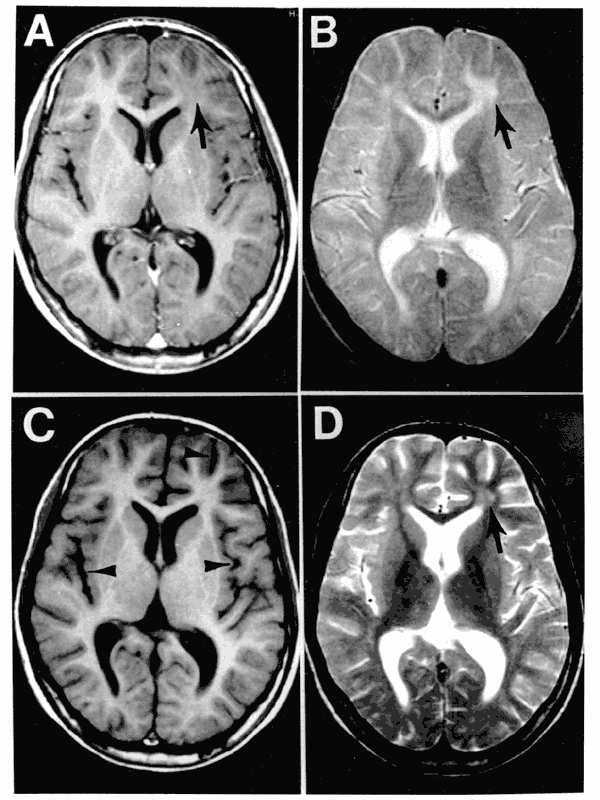

Basically, you get measles and then seem fine, but anywhere from months to 15+ years later, you develop brain inflammation, seizures, spasms, blindness, and coma, and it’s basically 100% fatal. The disease attacks your nerves and brain. There’s no treatment or cure, and it hurts the whole time you’re dying. It can take months or more of excruciating suffering to kill you. It’s similar to rabies, in that you lose all control and are guaranteed a protracted, painful death.